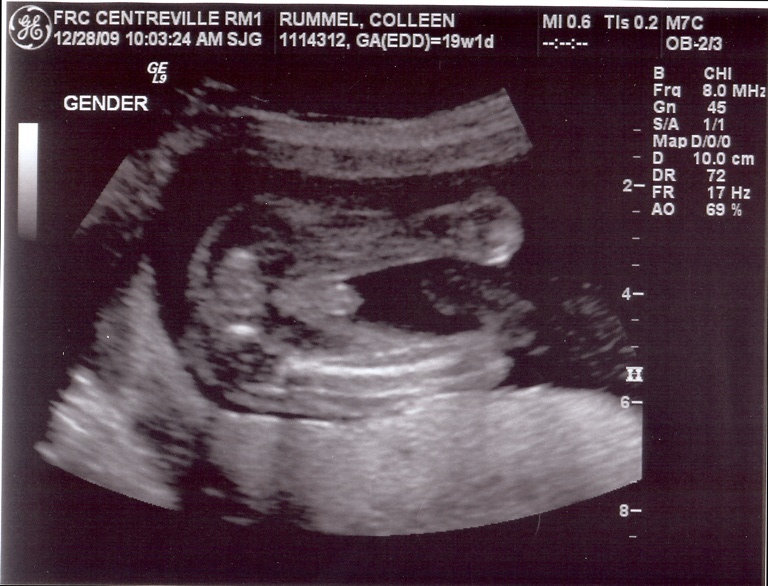

Yep, that sure is a boy! 🙂 Since you didn’t lead me astray in the daycare referral – who is your OB? Do you like him/her? I see you have Centreville on your sonogram. I had Tay in Virginia Hospital Center (Arlington) when we lived there, and my OBs are all right next door to there. Convenient for when I’m at work (I also work next door) but not so convenient for things like having babies and such. Would like to find someone down here…

So cute. And if you have to ask what he’s doing back there, you probably don’t want to know.